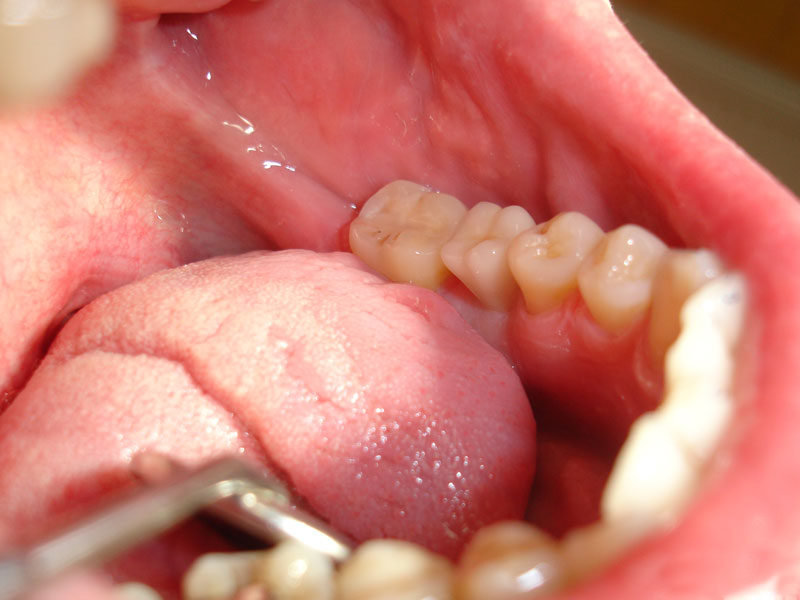

Folosim implanturi dentare WhiteSky si BlueSky, produse de firma Bredent, in Germania.

Prin tratamentul cu implanturi dentare se asigura refacerea arcadelor dentare atunci cand nu se doreste devitalizarea si slefuirea unor dinti, sau atunci cand nu sunt suficienti dinti pe care sa poata fi realizata o restaurare protetica fixa.

Implanturile dentare pot fi realizate din titan sau, mai nou, din zirconiu. Implanturile dentare din titan sunt implanturi folosite foarte des si care si-au dovedit rezistenta in timp.

Implanturile dentare de zirconiu sunt mai nou aparute, prezinta o biocompatibilitate si o estetica superiora celor din titan. Sunt indicate in special in zona frontala.